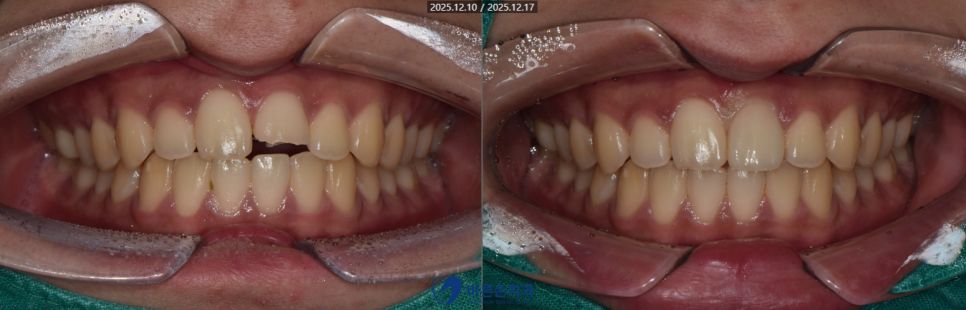

겨울철 넘어지셔서,

가운데 앞니 2개 중 하나가 반토막으로 부러졌네요..ㅠㅠ

완성된 보철물이 나와 세팅을 합니다.

다행히 원래 치아와 비슷하게

감쪽같이 치료가 잘 마무리 되었습니다.